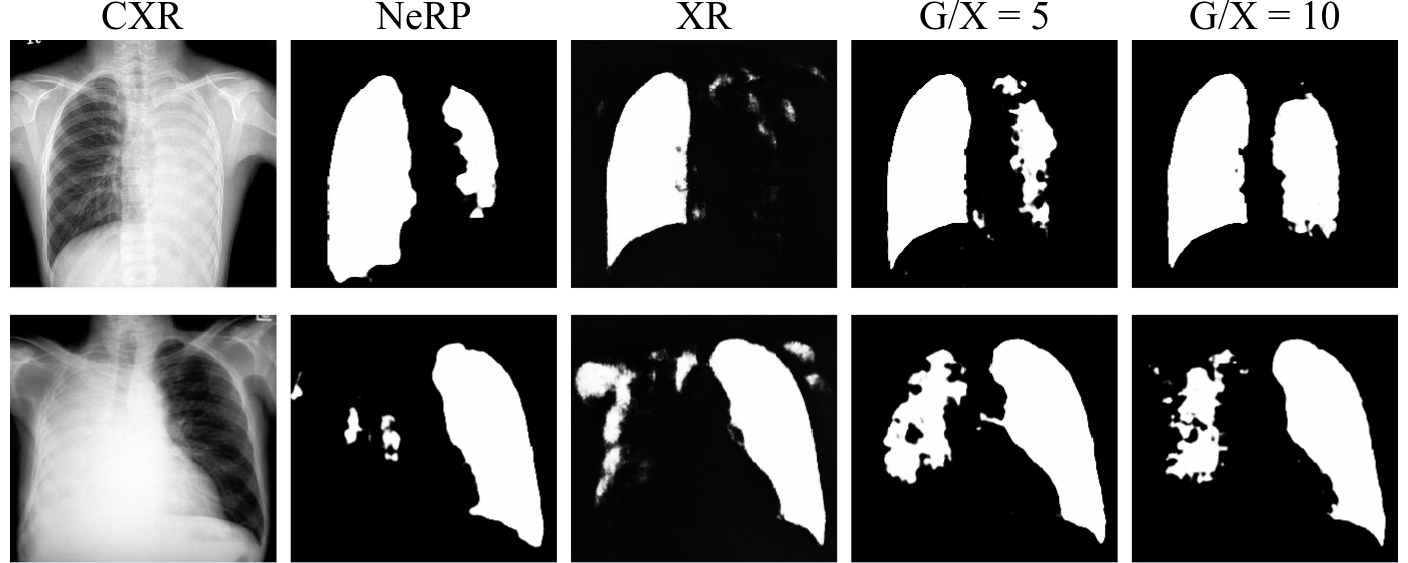

In this assessment, we gradually include portions of Chest XR with Lung annotation to train the U-Net and observe the performance over the quota of having extra annotated subsets of 2D XR data (see Fig. 4). Fig. 5 shows the Dice Scores on the separated test set for this setup. The horizontal axis represents the ratio (G/X) between the number of the generated images and XR images: means that the model was trained from XR only, and Inf means that model was trained from the generated images only. The results indicate that mixing the handful of annotated data with NeRP images yields better performance (up to 2%) over conventional DRR.

Furthermore, we choose extreme cases of Chest XR images with Pleural Effusion Lung Collapse, i.e., lung lobe on one side is filled by high contrast and brightness pixel values. As depicted in Fig. 6, combining NeRP and XR data promotes better lung regions even if the appearance of dark areas is partially missing.